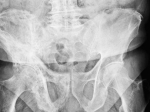

알렌드로네이트를 처방한 고관절 골절 환자를 대상으로 한 후향적 코호트 연구 결과 비치료군 대비 심혈관 질환이나 심근 경색, 뇌졸중으로 인한 사망 위험이 유의미하게 낮아졌다. 홍콩대학의 Ching-Lung Cheung 교수팀이 수행한 이 연구는 5월 9일 Journal of Bone and Mineral Research에 게재됐다.

연구진은 2005~2013년까지 고관절 골절로 진단받은 총 3만 4991명의 환자를 2016년 말까지 추적 조사했다. 이 중 골다공증 치료를 받은 환자는 4602명(13%)였다.